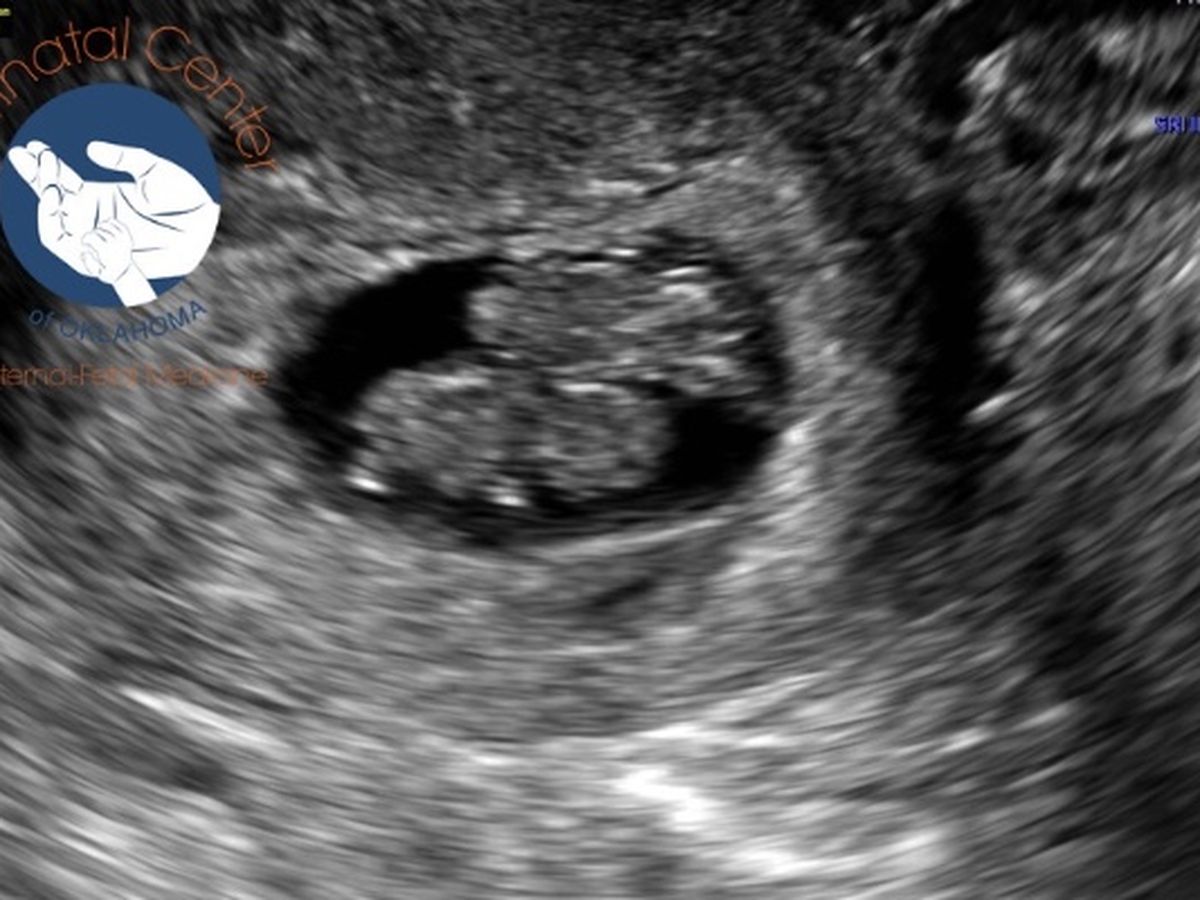

My best friend Meagen Quinton and her husband had been trying for quite some time to have a child. They experienced miscarriage after miscarriage. Finally, one absolutely wonderful day they found out they were expecting a new bundle of joy and were further along in this pregnancy than she had ever been. On their first appointment with the OBGYN they had their first ultrasound and were going to have twins. They were super excited. Along with this exciting news they also became scared for their little ones. The twins had a rare condition where they shared the same amniotic sac requiring them to see a specialist every two weeks due to the risk of cord entanglement. Life became tough with this unexpected expense. Insurance will only pay for so much. As they were preparing them self for arrival of their twins between 28-32 weeks they received another horrible blow. One of the twins was diagnosed with a neural tube defect called acrania wich is considered a 100% fatal defect and in order to save the other twin they must see a specialist in Houston Texas. The twins will undergo a lifesaving procedure which is not covered by insurance and will require unpaid time off as well as mounds of hospital bills. I am asking for your help please!!! We are raising only enough funds to help with the burden of time off work and travel expenses to Houston. Anything will help! Thank you for your time in reading my lengthy summary. Just an FYI this rare condition is considered 1 in a million.